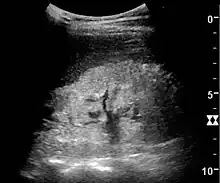

Ultrasound

Kidney ultrasonography is useful for diagnostic and prognostic purposes in chronic kidney disease. Whether the underlying pathologic change is glomerular sclerosis, tubular atrophy, interstitial fibrosis, or inflammation, the result is often increased echogenicity of the cortex. The echogenicity of the kidney should be related to the echogenicity of either the liver or the spleen (Figure 22 and Figure 23). Moreover, decreased kidney size and cortical thinning are also often seen and especially when disease progresses (Figure 24 and Figure 25). However, kidney size correlates to height, and short persons tend to have small kidneys; thus, kidney size as the only parameter is not reliable.[54]